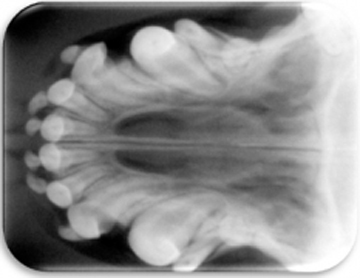

- Radiográfico (analógico y digital)

El diagnóstico clínico oral es de suma importancia ya que el plan de tratamiento y el pronóstico dependen de un certero y profundo análisis de los signos de la cavidad oral. Nuestra principal preocupación es atender los problemas que se encuentran en cavidad oral pero además siempre realizamos un detallado análisis de la función general del paciente. En nuestro centro revisamos de manera general a la mascota detectando cualquier problema sistémico. Contamos con un laboratorio de análisis clínicos en donde se realizan biometría hemática, química sanguínea, examen general de orina y pruebas para detección de enfermedades virales y de otros microorganismos. Contamos también con un laboratorio de histopatología en donde se revisa el material biológico para la detección y el diagnóstico de cambios morfológicos y lesiones en los tejidos. En lo que respecta al diagnóstico de la boca, contamos con un expediente donde se vacía toda la información dental y bucal de tal manera que mantenemos el control del tratamiento odontológico desde el inicio hasta el final y en donde el propietario o el médico que nos recomienda puede revisar en detalle toda la información recabada. Contamos con todo el instrumental y el equipo necesario para el diagnóstico de el aparato estomatognático (cavidad oral con dientes, tejidos de sostén y tejidos blandos, además de las estructuras relacionadas como articulación temporomandibular, cavidad nasal, cavidad orbitaria, etc.). Contamos con luz similar a la ultravioleta para diagnóstico de lesiones dentales por transluminación, pulpómetro para diagnóstico de vitalidad pulpar, localizador de ápices para tratamiento de conductos y equipo radiográfico tanto analógico como digital.